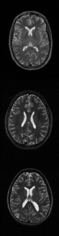

Convolves the image with a Gaussian kernel wherein the Gaussian has a standard deviation specified by the user (GUI field "sigma") and the kernel width in each dimension is 6 times the standard deviation of the Gaussian.-

- Set the sigma value to control the amount of blur. Larger sigma = more blur.